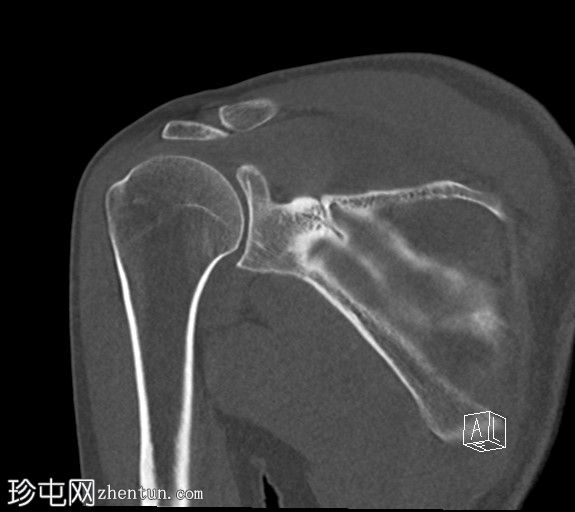

矢状位

非增强

CT显示肱骨头后外侧缘存在缺损及骨碎片,提示Hill-Sachs损伤。

右侧肩胛盂前下缘可见一小块骨碎片,提示Bankart损伤。

肩关节前脱位比后脱位更常见。

反复肩关节脱位时应考虑Hill-Sachs损伤。

若在前盂唇发现骨碎片,则应考虑Bankart损伤。